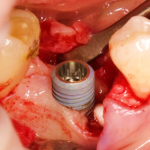

Для решения поставленной клинической задачи мы выбрали имплантационную систему Xive. Из имеющихся у нас трёх имплантационных систем, она лучше всего подходит для немедленной имплантации и немедленной нагрузки, и вот, почему:

В процессе ирригации лунки промываются, что позволило нам еще раз подтвердить ранее сделанные выводы. С помощью аналогов имплантатов, входящих в хирургический набор Xive, мы проверили возможность стабилизации имплантатов в будущих лунках. Исходя из правил подбора и позиционирования имплантатов (я очень рекомендую почитать об этом здесь>>) мы остановились на Xive S диаметром 3,4 мм и длиной 13 мм.

По ряду уже упомянутых выше причин, для решения этой клинической задачи мы выбрали имплантаты Xive. Лунки для них мы уже приготовили. возможную первичную стабильность оценили. Имплантаты мы установили с усилием чуть больше 15-20 Нсм — такого крутящего момента более, чем достаточно, особенно если учесть, что временные коронки будут соединяться между собой.